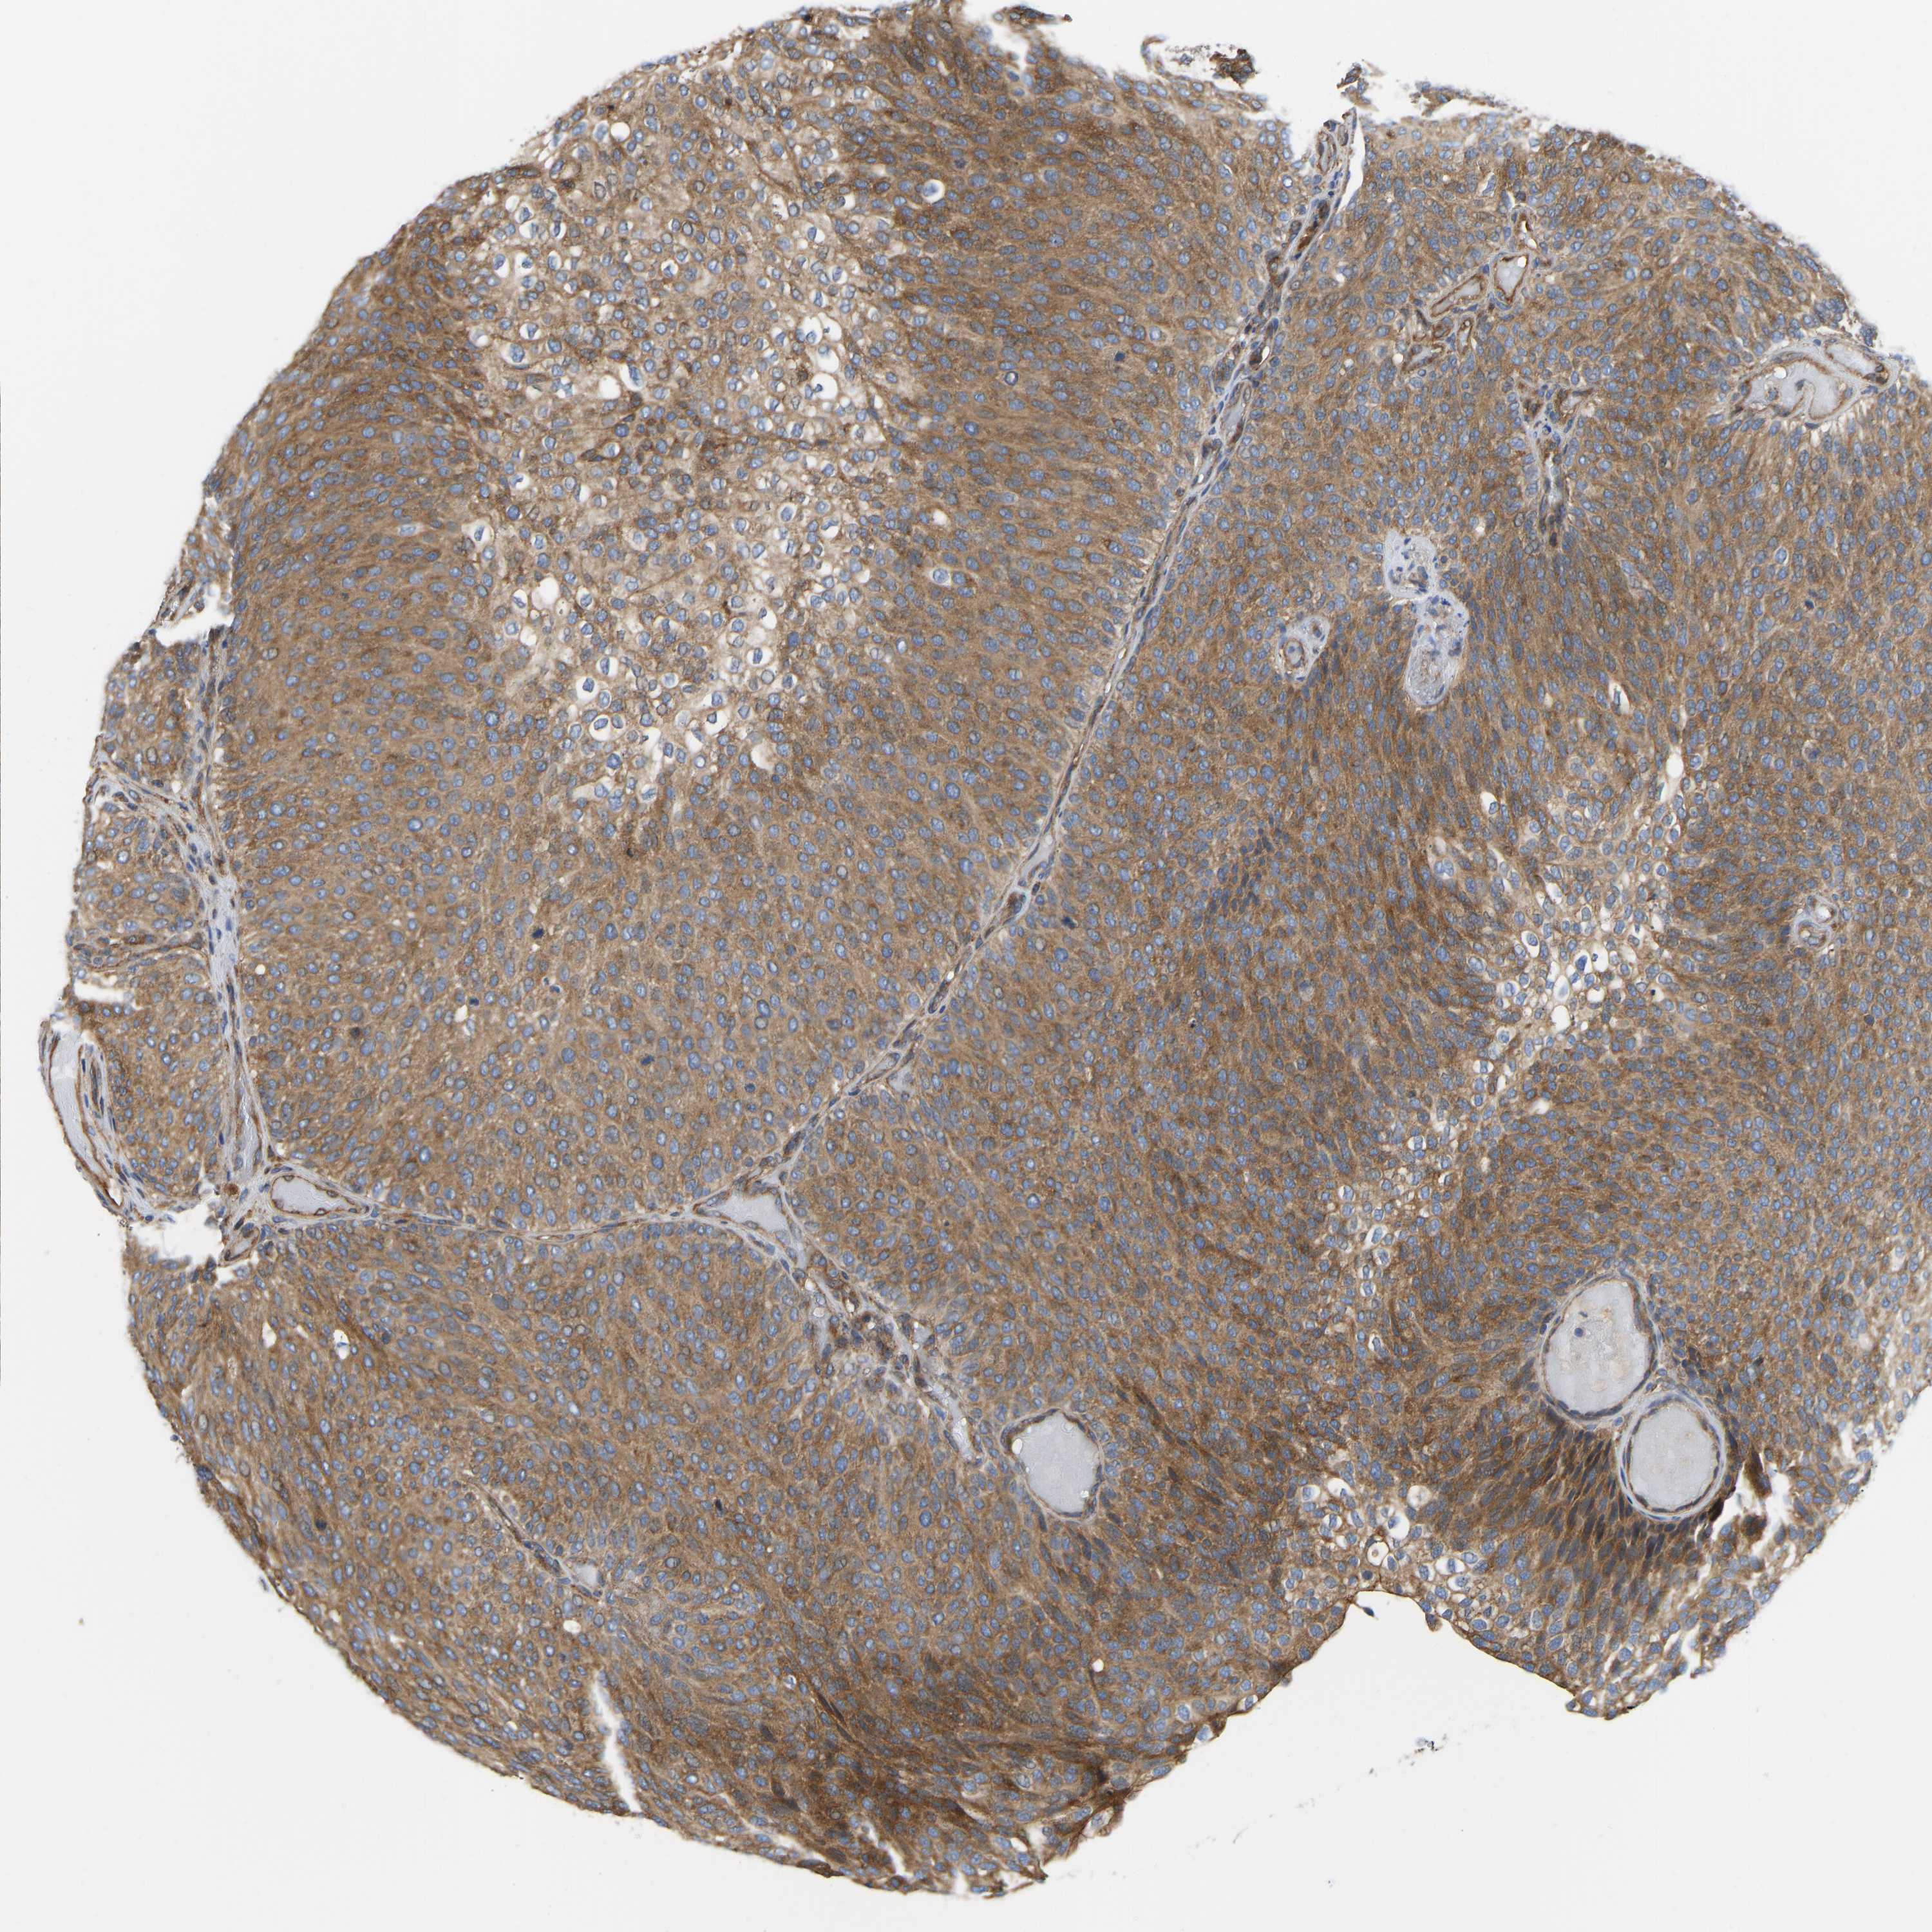

UROTHELIAL CANCER - Protein expressioni

A mouse-over function shows sample information and annotation data. Click on an image to view it in a full screen mode. Samples can be filtered based on level of antibody staining by selecting one or several of the following categories: high, medium, low and not detected. The assay and annotation is described here.

Note that samples used for immunohistochemistry by the Human Protein Atlas do not correspond to samples in the TCGA dataset.

Antibody stainingi

Antibody staining in the annotated cell types in the current human tissue is reported as not detected, low, medium, or high, based on conventional immunohistochemistry profiling in selected tissues. This score is based on the combination of the staining intensity and fraction of stained cells.

Each image is clickable and will lead to virtual microscopy that enables deeper exploration of all samples and also displays staining intensity scores, fraction scores and subcellular localization as well as patient and tissue information for each sample.

Antibody HPA004747

Antibody HPA004886

Antibody CAB019322

Staining

High

Medium

Low

Not detected

Intensity

Strong

Moderate

Weak

Negative

Quantity

>75%

75%-25%

<25%

None

Location

Nuclear

Cytoplasmic/membranous

Cytoplasmic/membranous,nuclear

Urothelial carcinoma, High grade

Urothelial carcinoma, Low grade